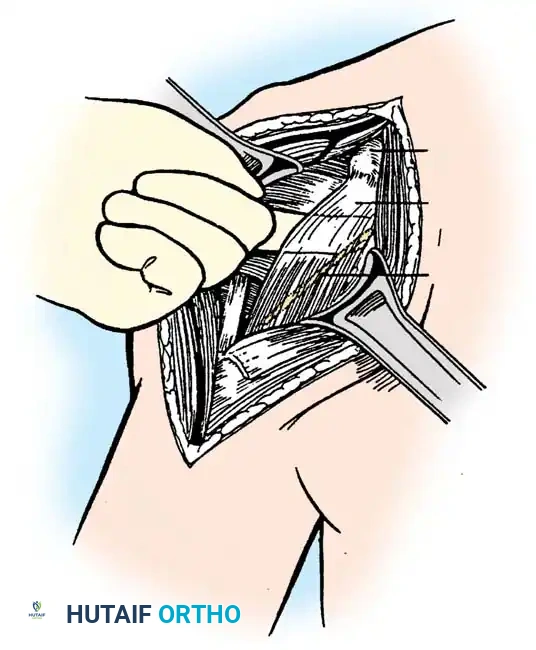

- Triceps Management: Several options exist, including a triceps-reflecting approach (Bryan-Morrey), a triceps-splitting approach, or a triceps-sparing approach. The Bryan-Morrey approach involves reflecting the triceps from medial to lateral in continuity with the anconeus and forearm fascia.

2. Joint Preparation

The tip of the olecranon is excised to facilitate access to the medullary canal. The distal humerus is prepared by resecting the trochlea and capitellum, preserving the epicondyles if possible to maintain collateral ligament attachments (though less critical in linked designs).

3. Canal Preparation and Implantation

The humeral and ulnar canals are sequentially broached.

- A cement restrictor is placed in both canals.

- Antibiotic-loaded polymethylmethacrylate (PMMA) bone cement is injected in a retrograde fashion.

- The components are inserted, and the articulation is linked using the manufacturer-specific locking pin mechanism.

Surgical Warning: The ulnar component must be inserted with precise rotational alignment. Malrotation will lead to eccentric wear of the polyethylene bushings and early catastrophic failure of the linkage mechanism.

4. Closure

The triceps mechanism is meticulously repaired using heavy non-absorbable sutures through drill holes in the proximal ulna. The ulnar nerve is secured in a subcutaneous anterior transposed position, ensuring no fascial bands compress it.